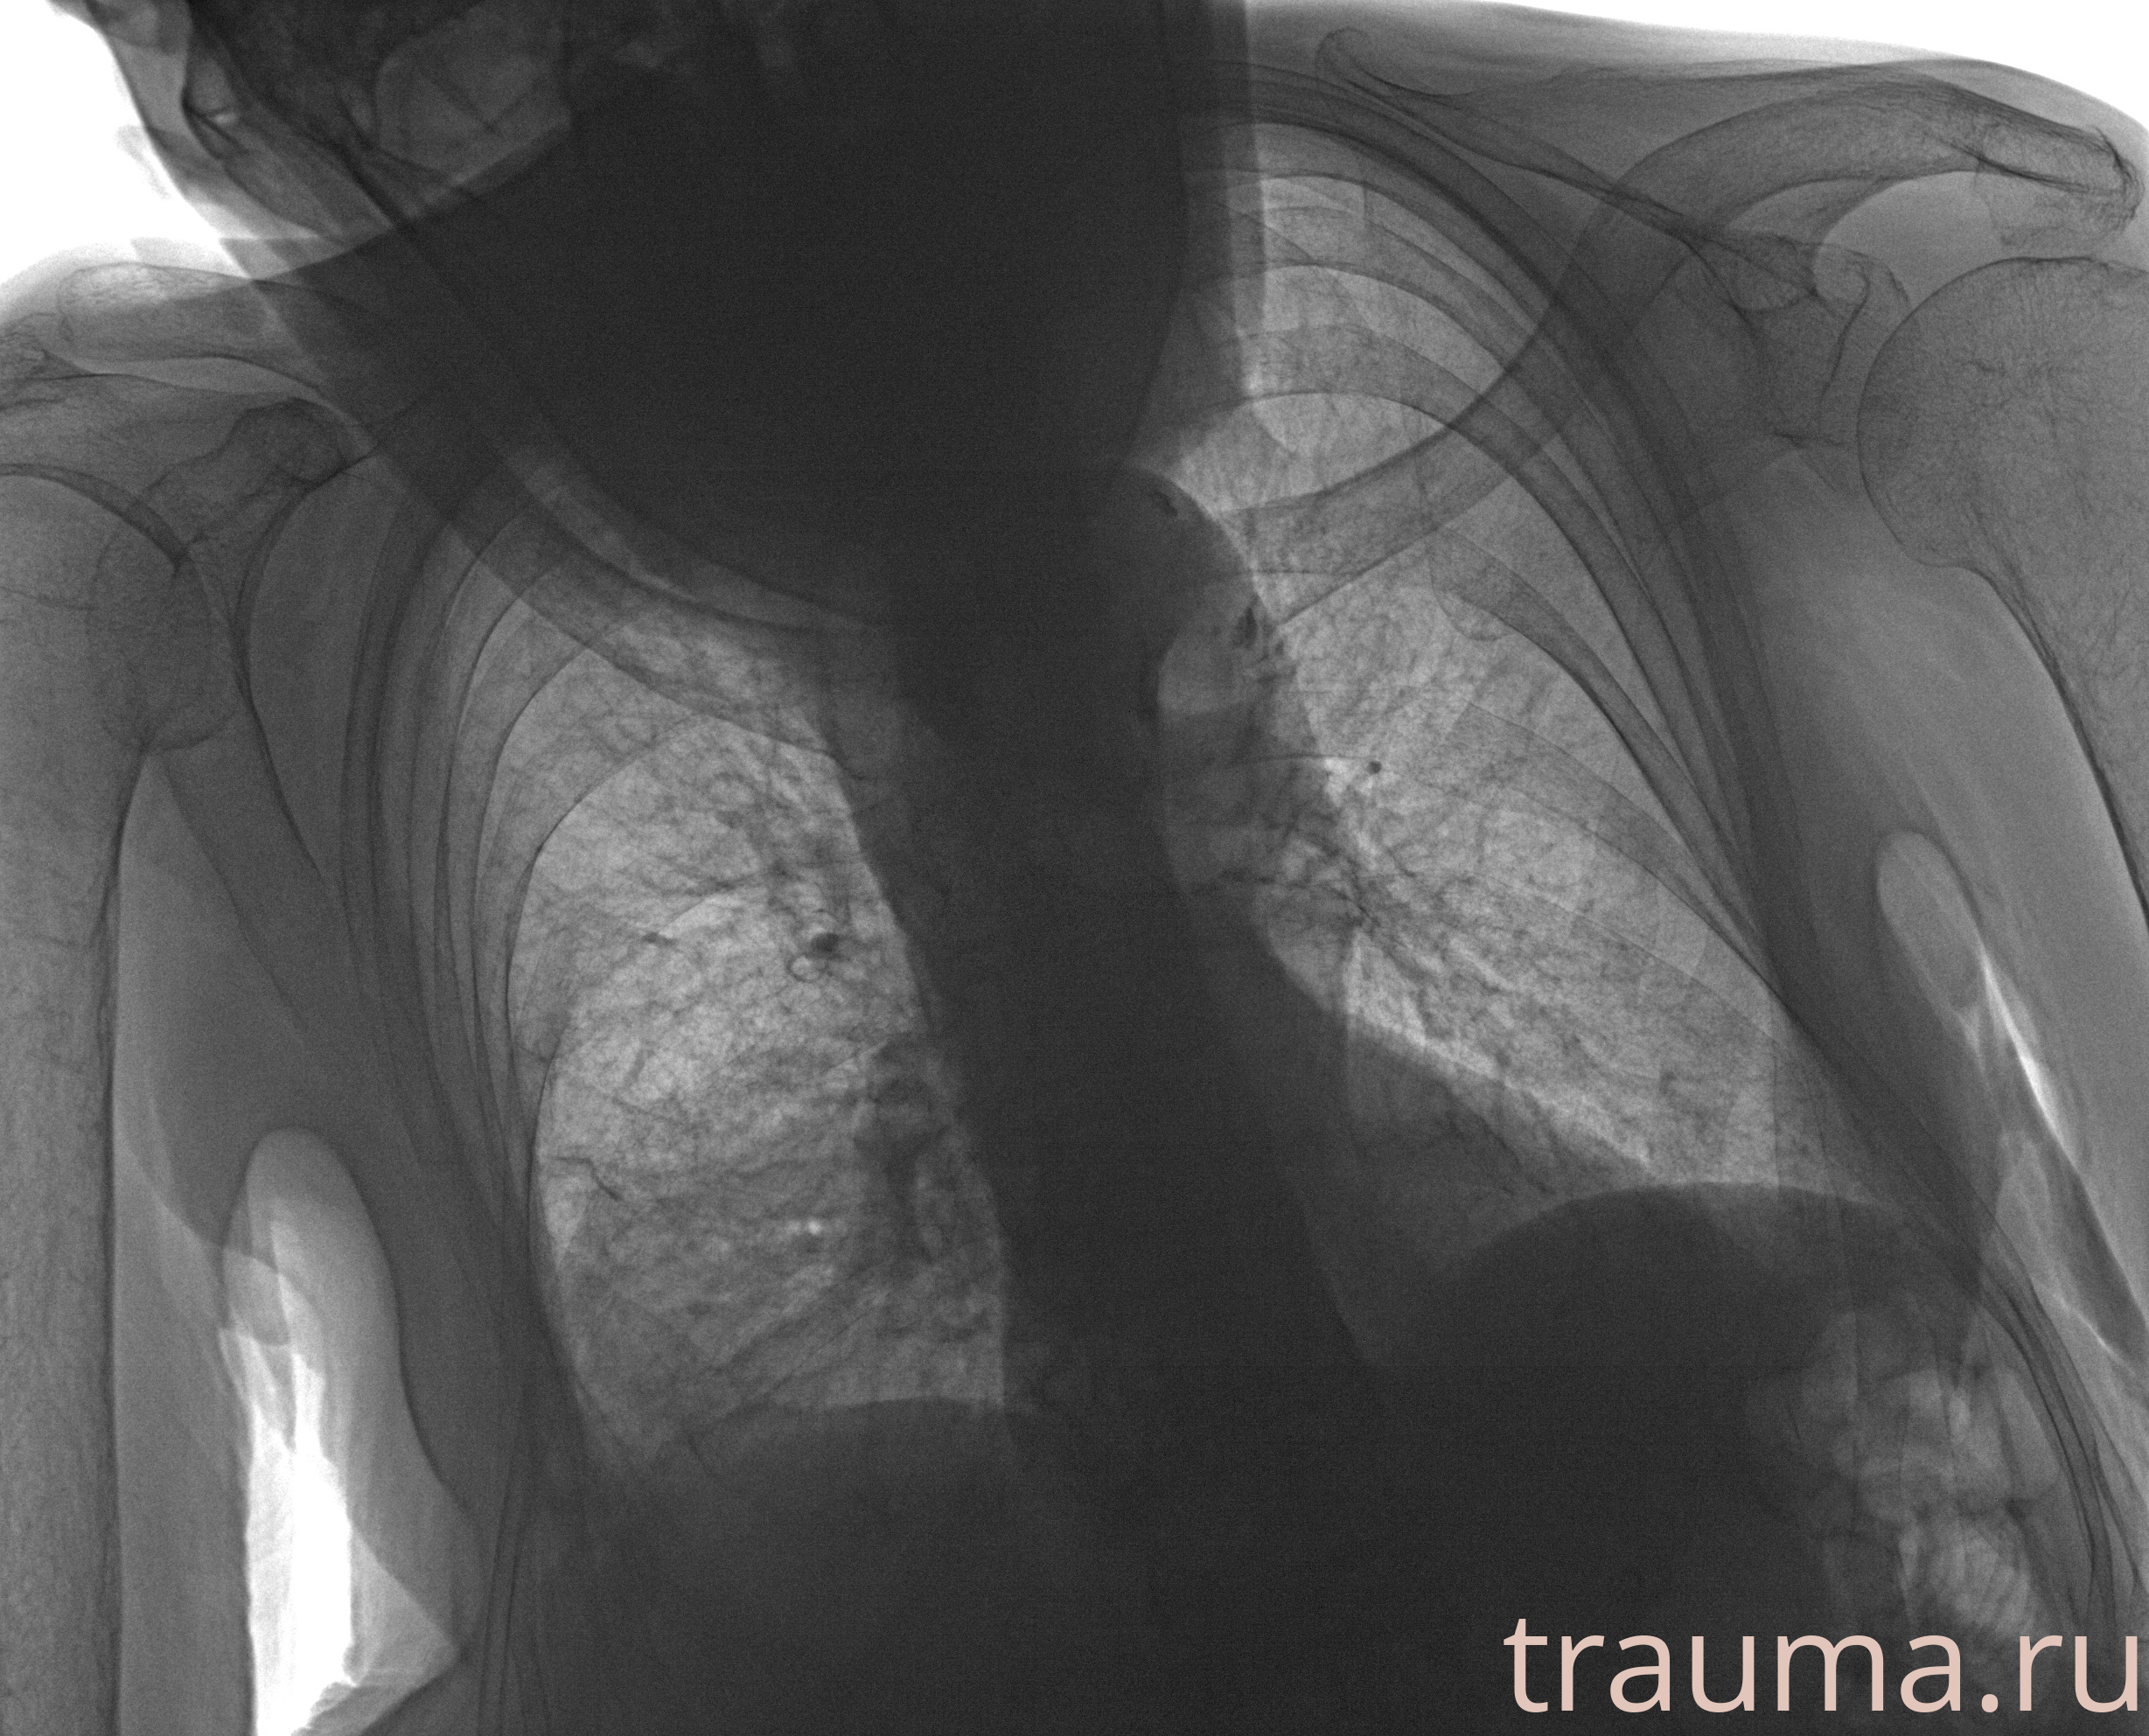

Рентгенограммы

Рентген на дому: по вашему адресу приезжает врач-рентгенолог, травматолог-ортопед с мобильным рентгеновским аппаратом, проводит диагностику травмы или заболевания, делает необходимые рентгенограммы, дает рекомендации по дальнейшему лечению. Получить качественные снимки в домашних условиях возможно благодаря уникальной методике, разработанной МосРентген Центром для института  Склифосовского